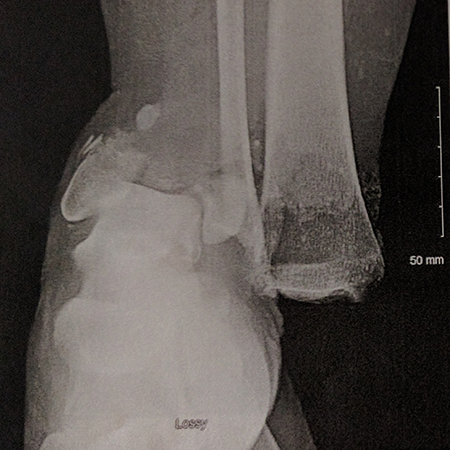

As she was being hoisted up and over the wall, Miriam suddenly felt like this particular challenge was not something her body was meant to do, so she announced she would jump down and walk around the wall. Unfortunately, the long drop back onto the soft, muddy ground put all of her body weight onto her leg and ankle at an odd angle, causing her joint to dislocate and several bones in her ankle to break quite severely. The injury was made even worse by significant surrounding tissue wounds and open contamination from the mud. With the help of event organizers, Miriam was transported to a local hospital, where the doctor attempted to stop the bleeding and closed her wound to prepare her for transfer to Massachusetts General Hospital three days later.

At Mass General, Miriam received care from a team comprised of an orthopedic trauma surgeon, plastic surgeon Kyle Eberlin, MD, and countless nurses, physician assistants and physical therapists. Her team cleaned out her wound further, placed a metal implant designed to aid healing and support bone growth, and constructed a flap meant to cover the wound area. Following her surgeries at Mass General, Miriam was transferred to the Spaulding Rehabilitation Network and then cleared for release six weeks after the injury.

After nine surgeries, Miriam began to grow despondent; the bone and tissue in the area of her injury were dying, and her leg was not healing well. Miriam decided to research alternative treatments and approaches, and sought a second opinion on her surgical plan from the Chief Emeritus of Mass General's Foot & Ankle Service, Christopher DiGiovanni, MD.

Miriam met with Dr. DiGiovanni and was encouraged by his confident, optimistic approach and expertise. She says that he listened to her concerns, expressed a willingness to take her treatment in a new direction, and collaborated with her on the care plan. For her next orthopedic surgery, Miriam’s metal implant was removed by Dr. DiGiovanni, and a three-dimensional external fixation device was attached to her leg. External fixation protects and stabilizes the affected bones and encourages fusion and growth, but can be less prone to infection, since it is largely outside the body. Miriam thought of the fixator as an extreme form of body jewelry, and so she asked Dr. DiGiovanni if she could add some “bling.” His team obliged by including a shiny gold-colored ring in the middle of the device.

Next, Miriam underwent a bone transplant with Dr. DiGiovanni, and was fitted with a special, three-dimensional Taylor spatial frame device on her lower leg. With a few alignment adjustments and the gradual removal of hardware, the bones moved into their proper positions and Miriam was on the road to recovery. She fused what was left of the bones in her ankle and lower leg, allowing her to keep her foot and have some function and stability, but there was only 60-65% of her native bone left in the area to do the support work required to stand and walk safely and steadily. With Dr. DiGiovanni's guidance, she soon discovered a new type of prosthetic device being developed across the country that would allow her to help load the injured ankle without compromising fixation or progressive mobilization. At that time, Dr. DiGiovanni had had two other patients with similarly complex foot problems who had tried the brace, and it seemed to help their healing process.